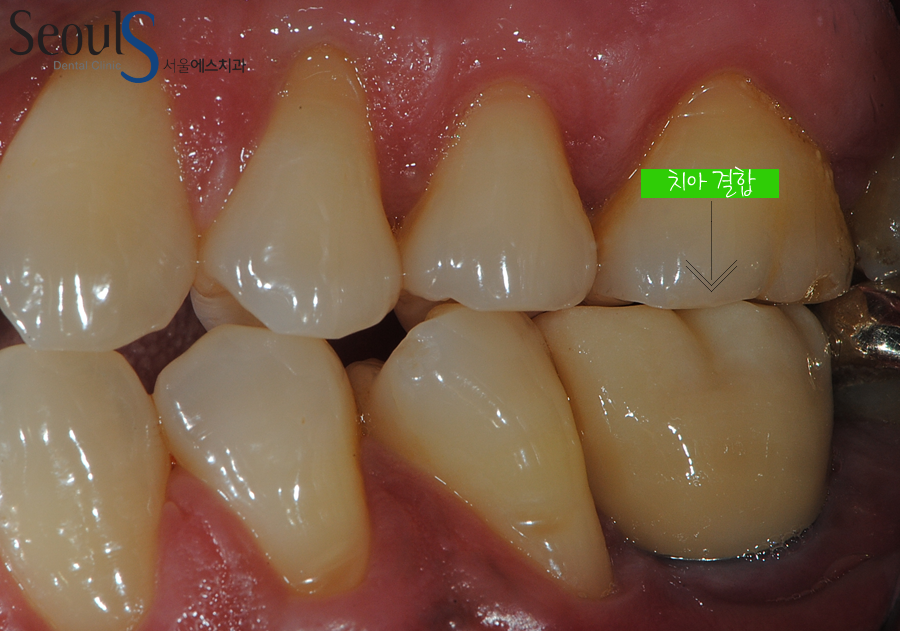

임시치아 과정을 거쳐 최종 이를 결합한 모습입니다

이쁘게 치료가 마무리된 모습이죠

측면에서 본 치아 모습입니다

보철물 결합 후 모습으로